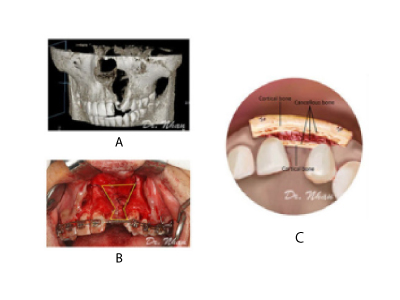

Cấy ghép Implant xương gò má cải tiến cho người tiêu xương trầm trọng (2014). Công trình đã được báo cáo tại hội nghị quốc tế về Phẫu thuật Miệng và Hàm Mặt (ICOMS) tại Úc 2015, Hồng Kông 2017 và công bố tóm tắt trên tạp chí International Journal of Oral and Maxillofacial Surgery, 2015 là tạp chí thuộc Hiệp hội quốc tế về Phẫu thuật Miệng và Hàm Mặt (IAOMS)

Cấy ghép Implant xương gò má cho bệnh nhân bị tiêu xương hàm trên trầm trọng

Bệnh nhân L.N.L có xương hàm trên bị tiêu trầm trọng cả theo chiều dọc và chiều ngang, chỉ còn một vài milimet, vùng răng sau xương hàm xuống thấp. Ts.Bs Võ Văn Nhân đã thực hiện kỹ thuật cấy Implant xương gò má. Đây là phương pháp rất khó vì Implant có lộ trình dài, nằm gần các cấu trúc giải phẫu quan trọng như màng xoang hàm, thần kinh dưới ổ mắt, sàn ổ mắt,…